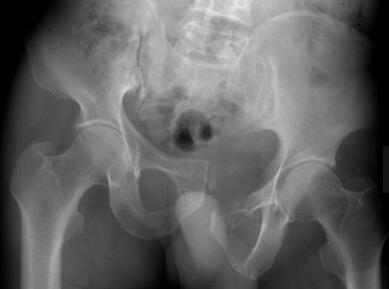

5、x线片:关节间隙不等宽,密度不均,骨盆倾斜,耻骨联合分离、上缘不等高,两侧髂骨不对称等。